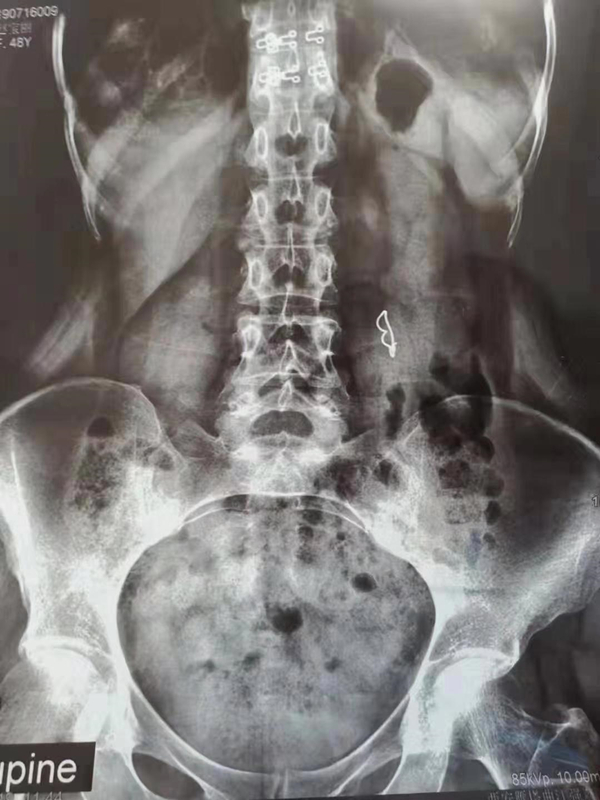

近日,我院消化内科内镜中心成功治愈一例复杂小肠异物嵌顿,患者是一名从渭南市远道而来的45岁女性患者,20余天前不慎将义齿吞入,在外院多次腹平片检查均发现义齿嵌顿在小肠,未下行。而义齿长期嵌顿可能引起穿孔等并发症,需要尽快取出。但是小肠位于胃和结肠之间,普通胃镜和结肠镜又难以到达,而外科手术又将造成较大的创伤。由于我院消化科与当地医院有长期医疗协作关系,所以病人被推荐到我院消化科就诊。消化科李路医生在见过病人,分析病情后,与王进海主任等商议后决定尝试进行小肠镜下异物取出术。

病人在麻醉医师进行全身麻醉后,李路医师指导王深皓医师开始操作,进镜后在屈氏韧带附近发现了义齿,而且义齿的挂钩已经扎入小肠壁。经过多次操作后挂钩终于脱离了肠壁,随着小肠镜的退出义齿顺利取了出来。这是一次成功的尝试,更是一次宝贵的经验,同时也是消化内科医护人员精诚协作的结果。